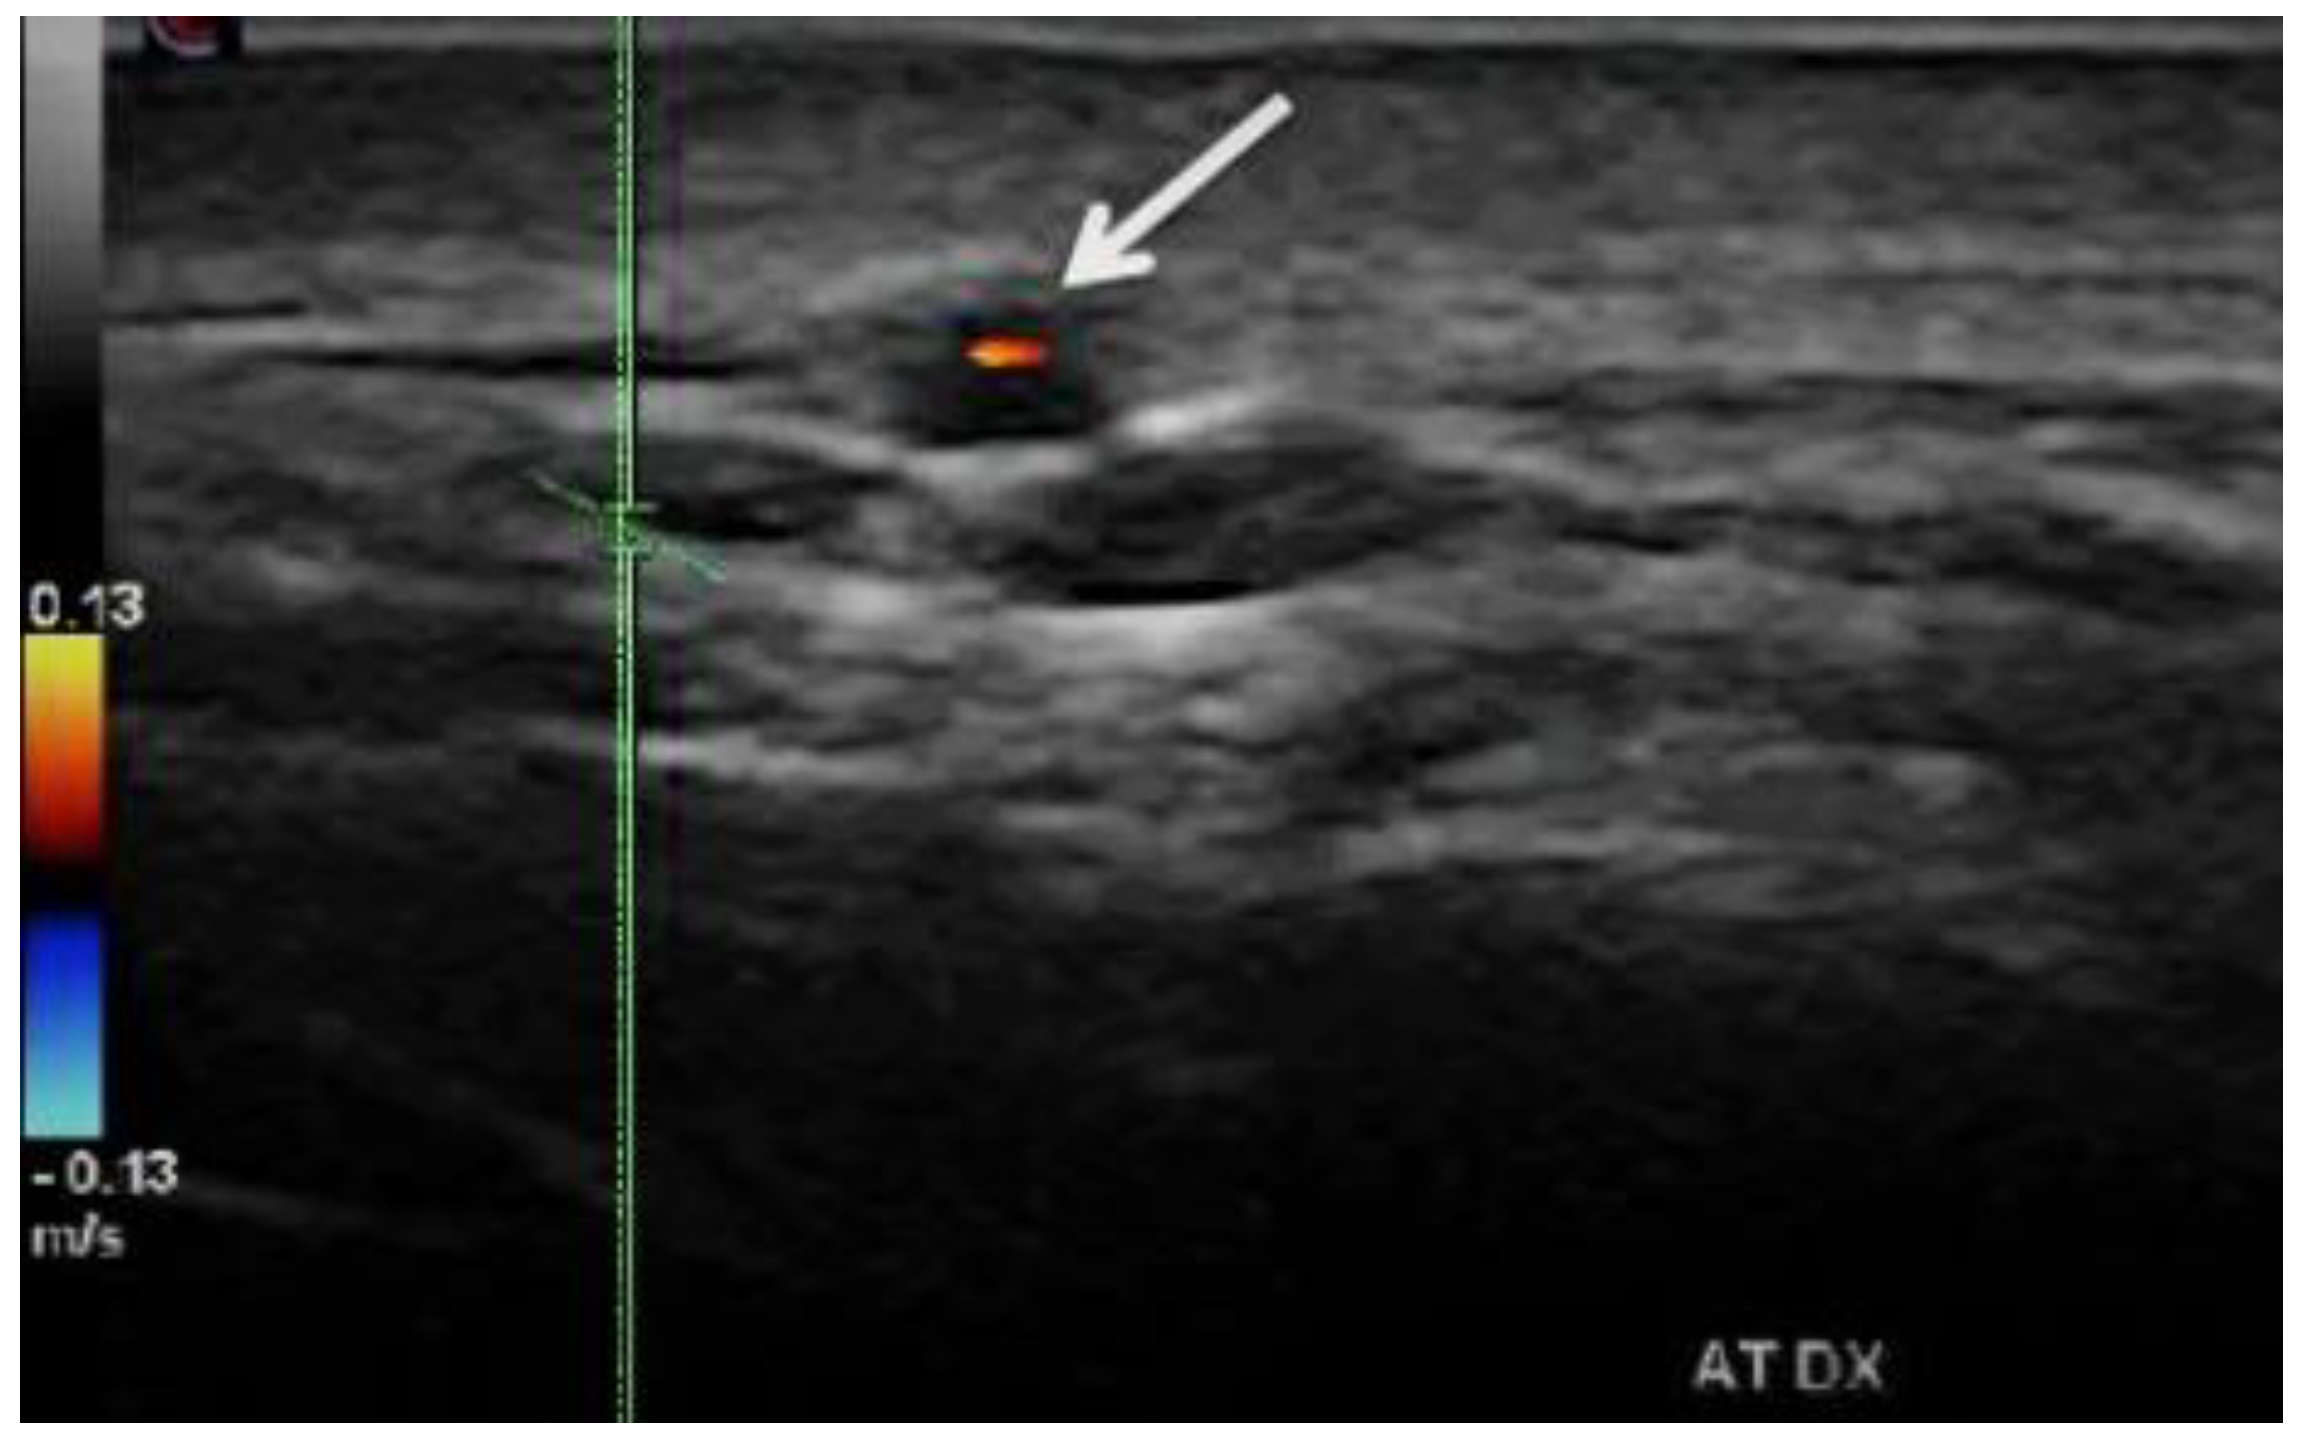

- “Dark halo” sign: An usually homogeneous, hypoechoic wall thickening surrounding the lumen of an inflamed artery. It is well outlined towards the luminal side, visible both in longitudinal and transverse planes, most commonly concentric in transverse.

- Stenoses are characterized by aliasing and persistent diastolic flow by colour Doppler US. The peak systolic velocity (PSV) assessed within the stenosis area by pulsed-wave Doppler US is two or more times greater than the PSV recorded in the prestenotic segment of the vessel, with turbulence at the level of stenosis, associated with diminished velocities distal to the stenosis [30,31,32,33,34,35,36,37,38,39,40,41] (Figure 3) [11].